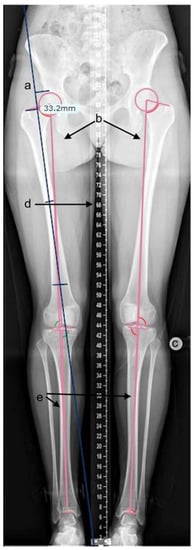

2.2. Radiographic Measurements